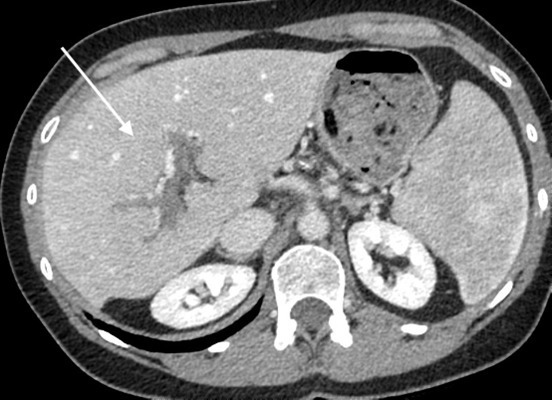

Rehaussement au temps artériel

Le foie est perfusé par la ou les artères hépatiques et la veine porte, celle-ci étant responsable d’environ trois quarts des apports sanguins. Les deux systèmes vasculaires se rejoignent pour perfuser le réseau sinusoïdal du foie. Il a été démontré qu’une baisse de la perfusion portale entraîne une augmentation compensatoire de la perfusion artérielle hépatique. Cet effet, parfois appelé «  effet tampon  », se traduit directement en imagerie par un hyper-rehaussement à la phase artérielle dans les territoires souffrant d’une baisse du débit sanguin portal.8 C’est un signe clé pour évoquer une maladie vasculaire du foie. L’hyper-rehaussement présente des limites nettes, respectant les territoires vasculaires (fig. 1). En cas de chute de la perfusion porte dans tout le foie, ce rehaussement est présent dans les régions sous-capsulaires. Il s’homogénéise aux temps veineux. La mise en évidence de ce signe doit faire rechercher toute cause de baisse de la perfusion portale (thrombose, compression, maladie microvasculaire, etc.).

Perfusion en mosaïque

Le rehaussement (ou perfusion) en mosaïque du foie est très évocateur d’une maladie vasculaire. Il correspond à un rehaussement hétérogène (dit en feuille de fougère), surtout visible en périphérie et dans le foie droit, en particulier aux temps précoces (artériel et portal), puis qui s’homogénéise au temps tardif (fig. 3). Cet aspect est pathognomonique d’une dilatation sinusoïdale. Il doit donc faire rechercher toute cause de perturbation du retour veineux hépatique (thrombose des veines hépatiques, cardiopathie surtout droite, etc.).